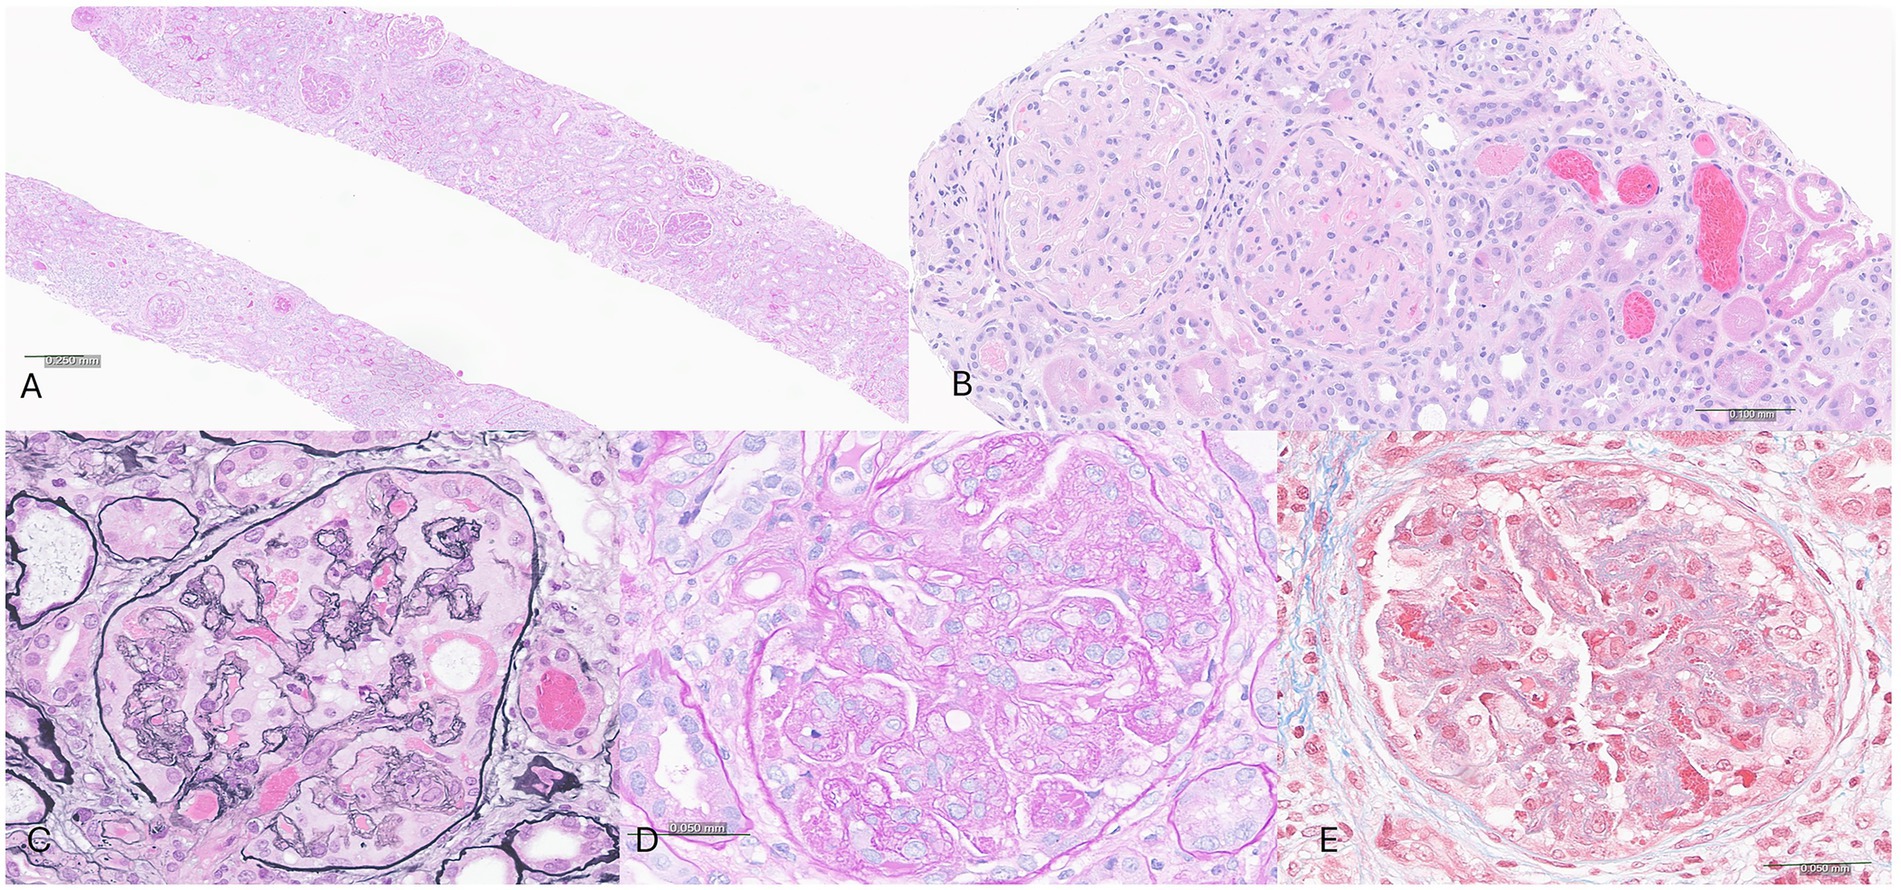

Gemcitabine-Induced Membranoproliferative Glomerulonephritis with Immune Complexes in a Patient with Metastatic Pancreatic Cancer

Gemcitabine is a widely used chemotherapeutic agent for pancreatic adenocarcinoma, that is associated with rare but serious renal complications including thrombotic microangiopathy (TMA). We report a unique case of biopsy-proven membranoproliferative glomerulonephritis (MPGN) with immune complex deposition in a woman receiving gemcitabine for metastatic pancreatic cancer. She developed new-onset hypertension, proteinuria, microscopic hematuria, and progressive renal dysfunction shortly following initiation of gemcitabine. Extensive autoimmune, complement, paraprotein, and viral serologies were unremarkable aside from a low haptoglobin. Kidney biopsy revealed an MPGN pattern with immune deposits. Gemcitabine was discontinued, and the patient was treated with corticosteroids and kidney-protective therapies targeting blood pressure and proteinuria reduction. Her proteinuria decreased significantly, and her renal function returned back to baseline. This case highlights a rare manifestation of gemcitabine-induced nephrotoxicity with immune complex MPGN, suggesting a possible novel mechanism of drug-associated glomerular injury.